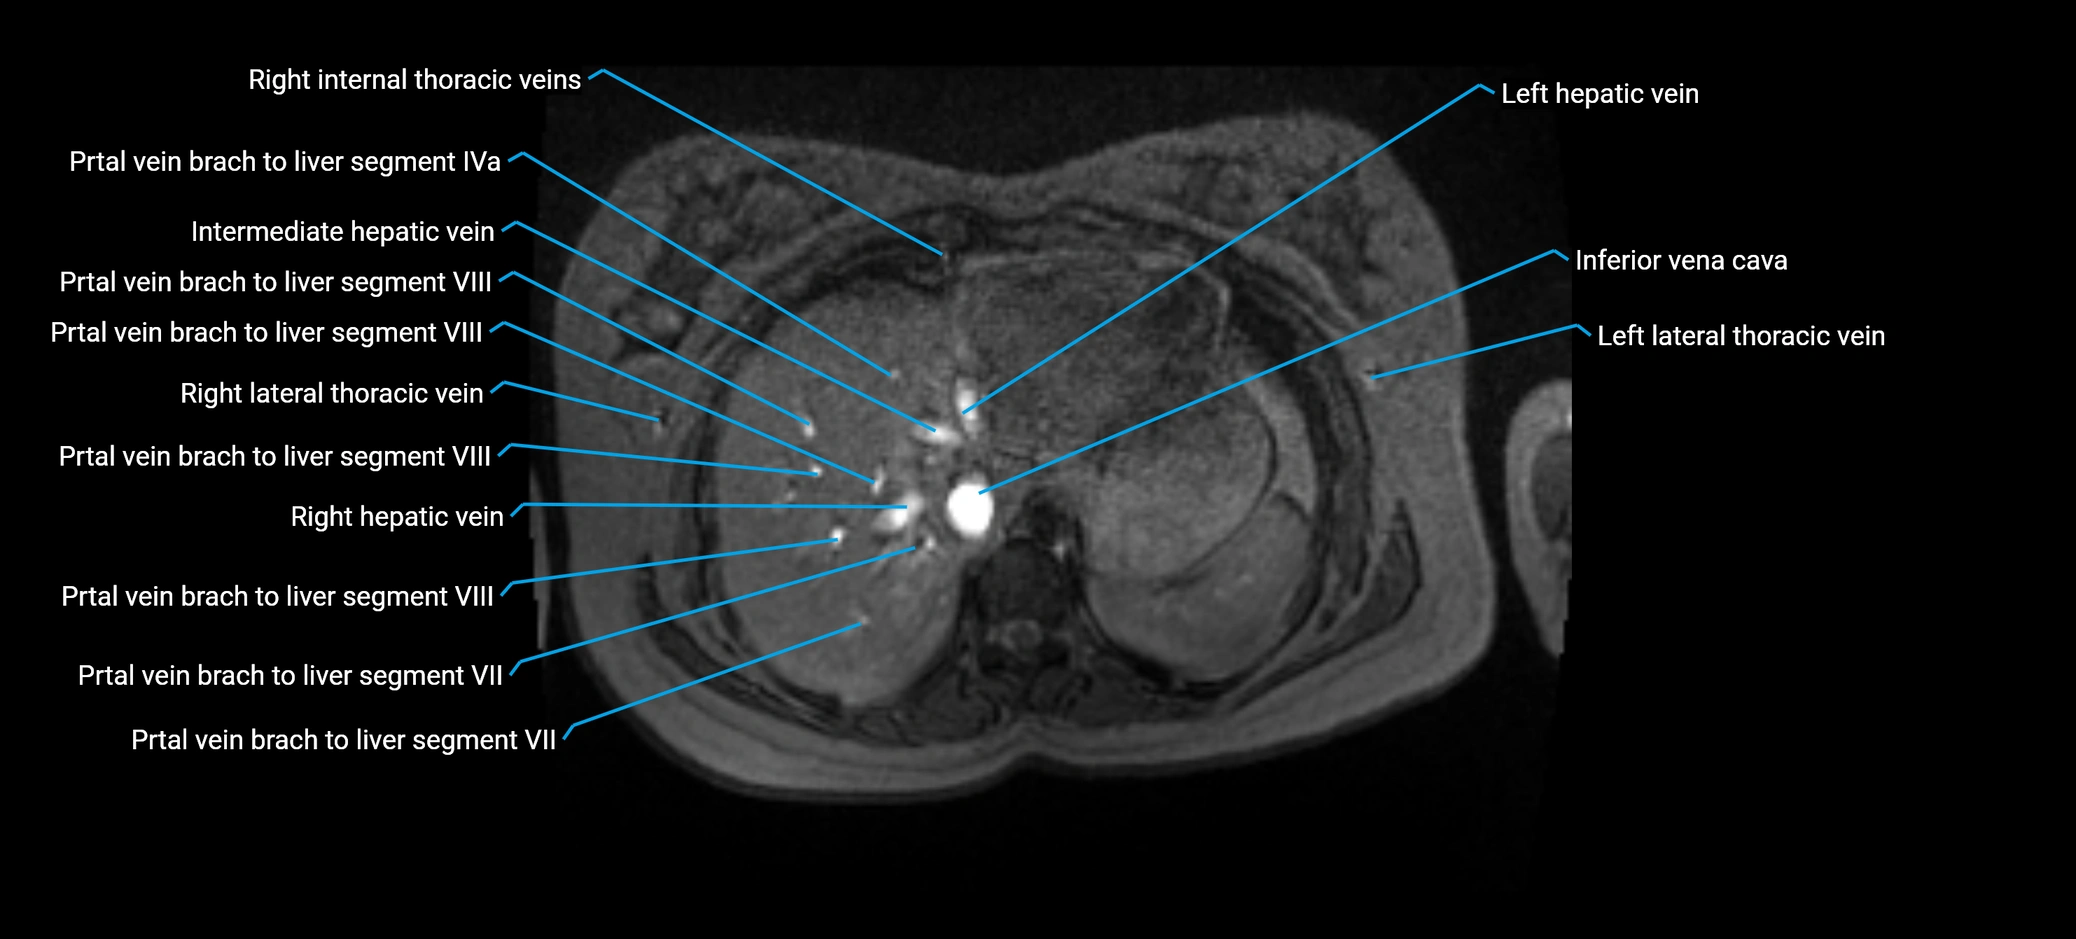

MRV TOF (Time-of-Flight MR Venography):

• Appears as a bright, high-signal vascular channel representing flowing blood

• Clearly shows branching pattern of right portal vein into anterior and posterior branches

• Best in coronal or axial reconstructions for segmental mapping

• No need for contrast, relies on flow-related enhancement

MRI image

image